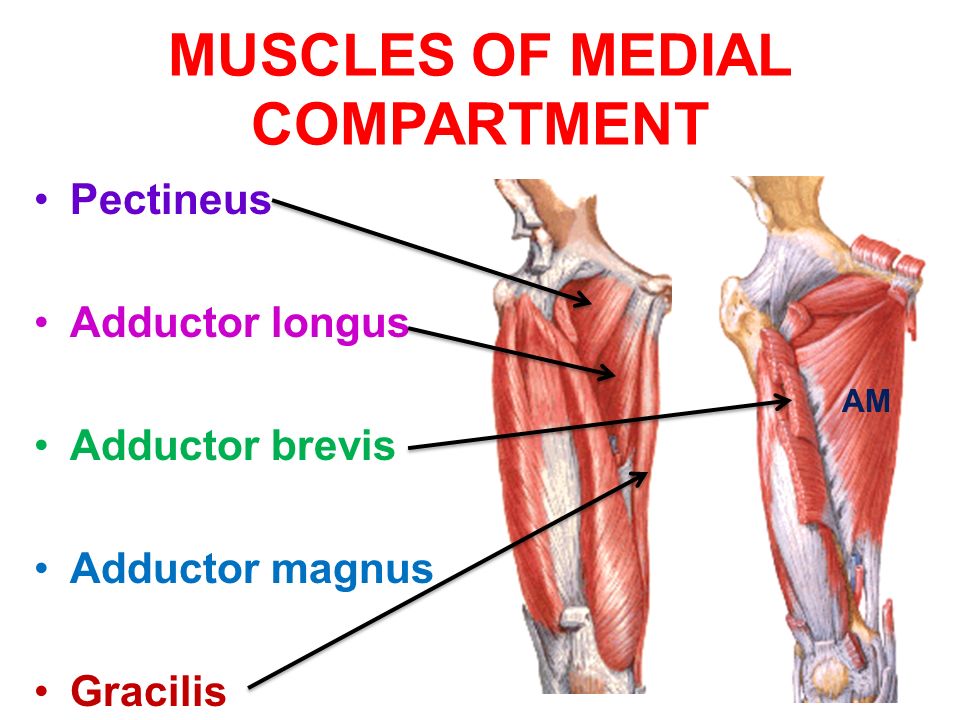

Анатомия и Функции Мышцы Adductor Magnus